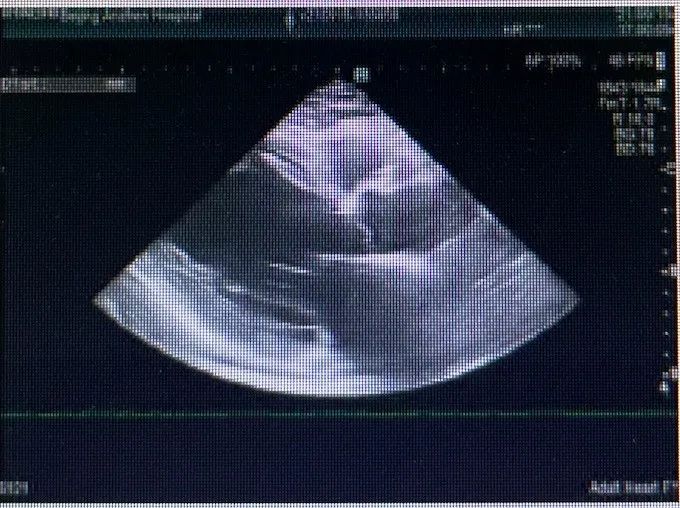

心脏彩超

舒张期主动脉瓣下见大量反流信号

缩流颈8mm

左室射血分数EF值: 40%

左室舒张末期内径(LVD):66 cm

主动脉瓣评估:左心增大,左心功能减低,二尖瓣反流(重度)、三尖瓣反流(轻度),肺动脉高压(轻度)并少许心包积液